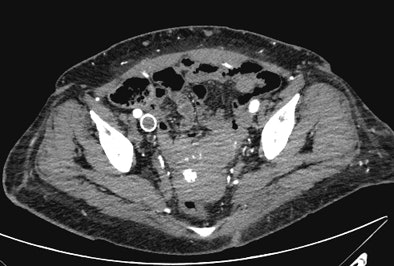

| Patient is in renal failure but not yet on dialysis. CTA was acquired at 80 kVp and 360 mAs following administration of 50 mL of 350 mg/mL contrast. Contrast density in the iliac arteries is > 400 HU. Radiation dose is 4.3 mSv. There is an incidental right iliac venous stent. Images courtesy of Dr. Barry Daly. |